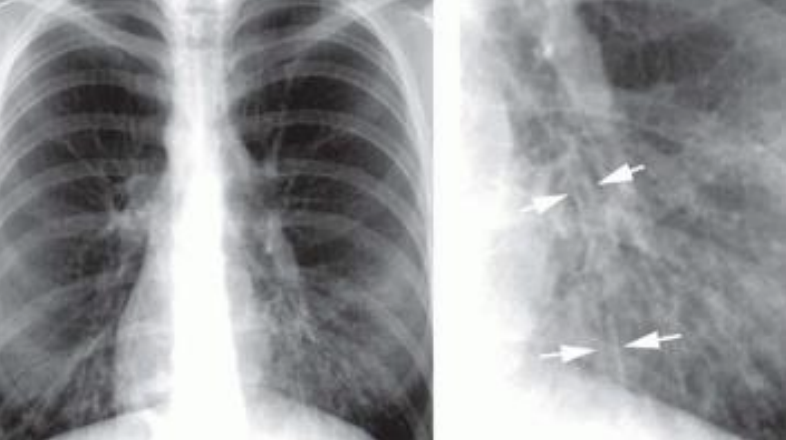

Aplanamiento del diafragma

Disfunción marcas broncovasculares

Hiperlucidez pulmonar

Corazón en gota

Rx enfisema